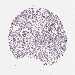

ARL14EP is validated prognostic, high expression is favorable in Kidney Renal Clear Cell Carcinoma (validation)

Best expression cut offi

When clicking on this number, the vertical dashed line indicating cut-off, the interactive survival plot, and the Kaplan-Meier curve will be adjusted to show results based on the best expression cut-off.

: 16

P scorei

N/A

5-year survival highi

5-year survival lowi

Average pTPM 17.3

Number of samples 100